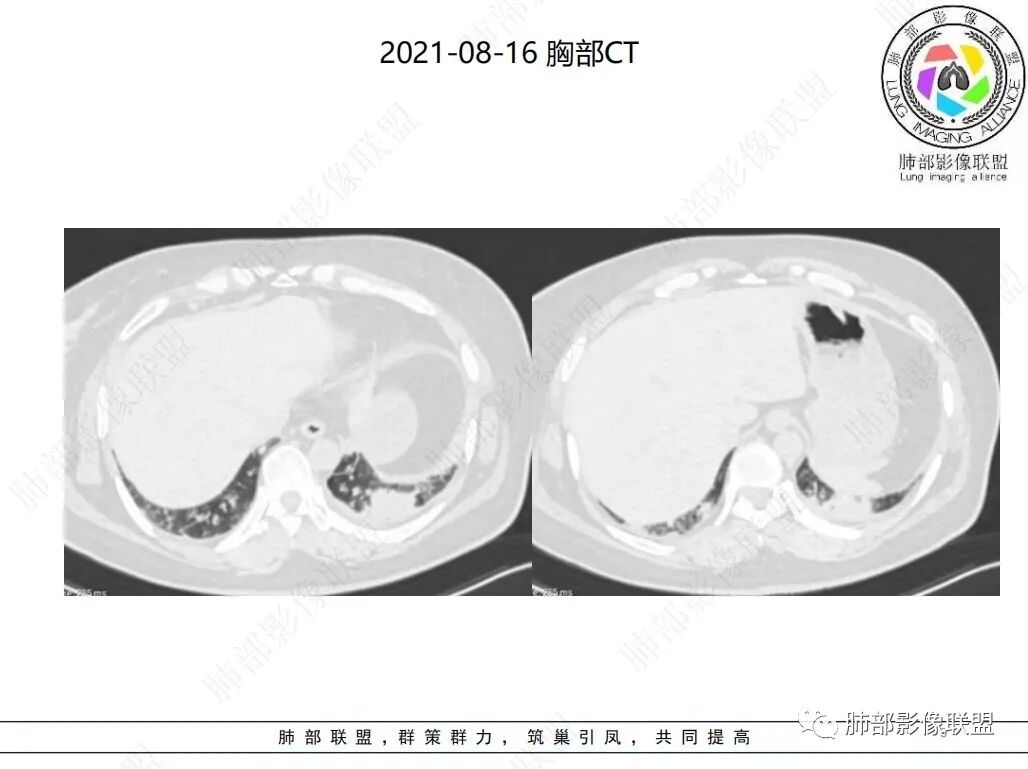

治疗后复查

3. 病灶在外周胸膜下为主,小叶间隔增厚,支气管壁增厚,部分细支气管可见闭塞,左肺下叶实变影。合并有鼻窦炎及肾功能不全,抗感染无吸收。

ANCA相关性血管炎肺部常被累及。最常见的为肺部结节,其中以支气管周围结节最多,其次是支气管扩张和胸腔积液以及肺出血和淋巴结肿大、肺气肿和空洞样病变等。由于肺内磨玻璃影、纤维条索影、斑片实变影、肺结节、网格状影、蜂窝状影、 肺大泡影、肺气肿、空洞、胸膜增厚、胸腔积液、 心包积液、纵膈淋巴结肿大等多种表现存在,极易误诊为肺部感染性疾病、间质性肺炎、肺结核及肺栓塞等疾病。